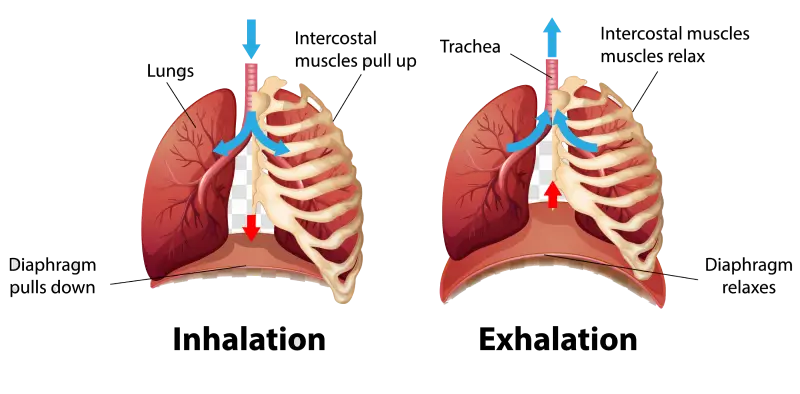

A veces hablamos de la zona lumbar como un “cilindro”. Esto significa que la columna vertebral se sitúa en el medio del cilindro y los músculos y vísceras alrededor de la columna crean una forma de cilindro. Cuando inhalamos y exhalamos y cuando “empujamos”, la presión y la geometría de este cilindro cambian. Esto afecta la estabilidad de la columna. La parte superior de este cilindro es un músculo llamado diafragma. El diafragma es quizás el músculo principal para la respiración, pero también juega un papel en la estabilidad de la columna y en la presión intraabdominal. Lógicamente, dado que el diafragma juega un papel en la estabilidad de la columna y en la respiración, ¡la respiración está vinculada a la estabilidad de la columna!

El dolor y las lesiones pueden afectar la forma en que nuestros músculos se activan a través de un mecanismo complejo en nuestro sistema nervioso. En un estado no lesionado, una persona debería poder contraer todos los músculos abdominales y de la columna lumbar a un nivel bajo para estabilizar la columna mientras mantiene una respiración y un habla adecuadas. Para algunas personas, estas cosas deben ocurrir por separado. Mantienen la respiración para estabilizar la columna o respiran libremente con un patrón descoordinado que no incluye una respiración profunda ni ninguna estabilización de la columna. Un estudio interesante publicado en el European Spine Journal investigó los patrones de respiración de personas con y sin dolor lumbar. Pidieron a los sujetos que estuvieran de pie y acostados y que realizaran tres tareas motoras diferentes. Lo interesante es que encontraron que las personas con dolor lumbar crónico tenían más probabilidades de tener patrones de respiración alterados. Esto era independiente de la gravedad del dolor. Esta respiración alterada se relaciona con un control neuromuscular alterado durante tareas simples. En otras palabras, las personas con dolor lumbar crónico tenían una capacidad reducida para apoyar su columna usando sus músculos. En particular, estas personas tienen una capacidad reducida para usar el diafragma correctamente, lo que resulta en dolor en el diafragma y en la espalda.

Respirar adecuadamente es importante para nuestras diversas funciones corporales que requieren oxígeno. También se ha discutido en relación con el estrés, la conexión mente-cuerpo y la relajación. Ahora sabemos que también se relaciona con la salud de la columna y la estabilidad de la columna.

Los profesionales harían bien en incorporar esto en su tratamiento del dolor lumbar, ayudando a las personas a identificar patrones de respiración defectuosos y ofreciendo estrategias para promover mejores hábitos. En resumen, el énfasis debe estar en elevar y expandir la caja torácica durante la inspiración, teniendo en cuenta la biomecánica de la columna vertebral y los patrones de movimiento. ¡El diafragma es, de hecho, parte del equipo!